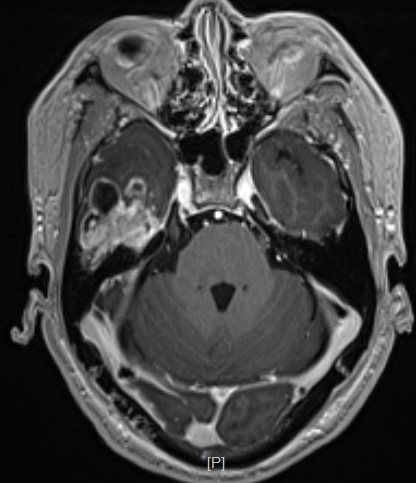

头部MR提示:右颞叶,岛叶及基底节区巨大占位,胶质母细胞瘤可能性大

矢状位

术前导航提示肿瘤与锥体束毗邻